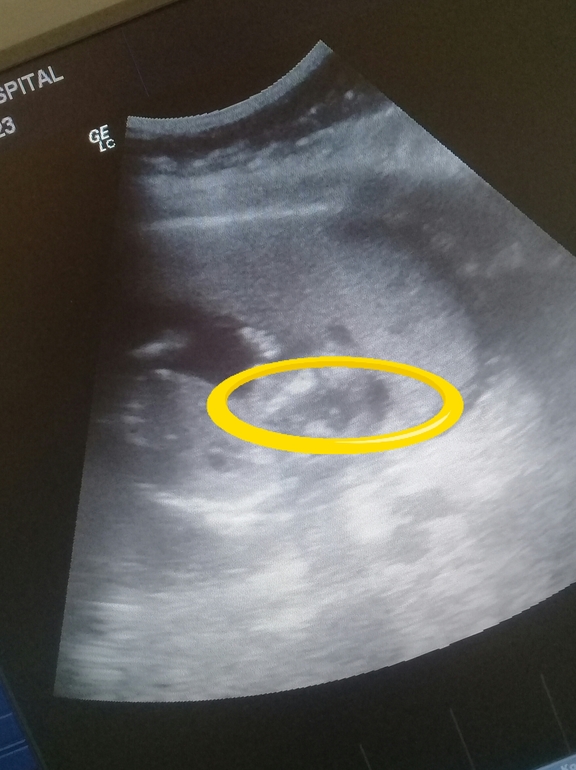

Вопросы про УЗИ, обследования и анализы: что, где, как, когда?Девочки, как думаете кто? Была на цервикометрии попросила глянуть сердечко , все хорошо.только фоточку с крохой не дали😢пришлось самой фоткать.интересно кто же там?

Непонятно, что где)) Обведите хотя бы область, куда смотреть 😊 и сколько недель?